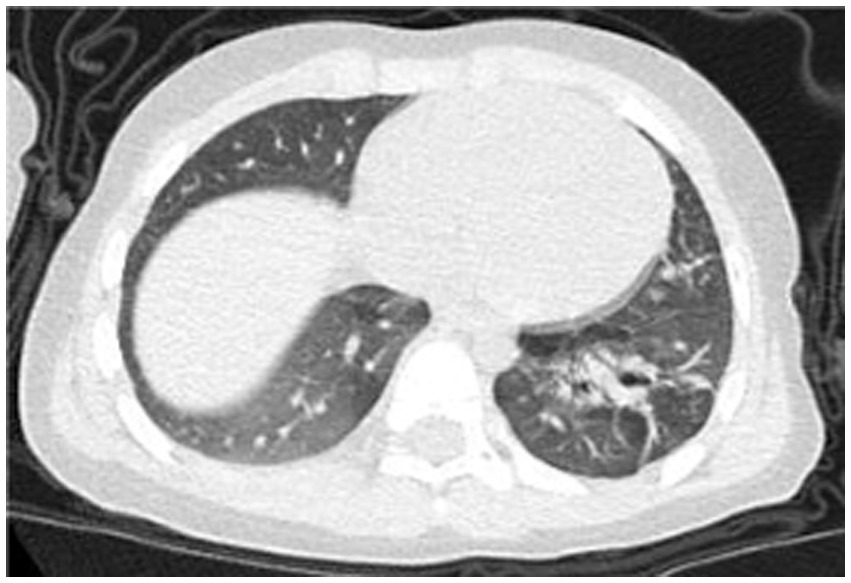

On day 32, the patient experienced worsened cough and developed respiratory distress. Chest CT (Figure 3) revealed left-sided pneumothorax with 40–50% lung compression, managed with thoracic drainage. Due to significant necrotic lung tissue and potential recurrent pneumothorax, surgical resection was advised but declined by the family. On day 41, recurrent fever prompted testing, revealing Mycoplasma pneumoniae via antigen detection on nasopharyngeal swabs using the colloidal gold method, treated with azithromycin (10 mg/kg/day intravenously for 3 days).

Figure 3

Chest CT scan on the 32th day of the illness.